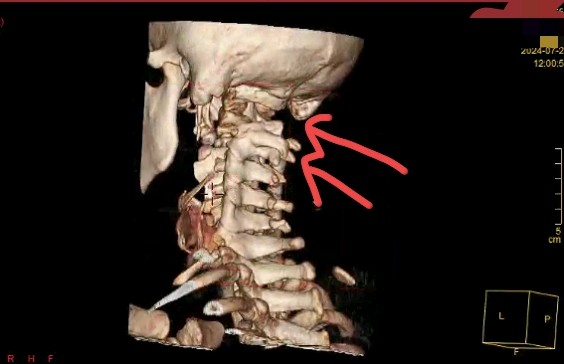

颈椎DR显示上位椎体分界不清,建议进一步完善颈椎CT:提示颅底凹陷,寰枕融合,上段椎体阻滞!

此类情况属于罕见先天发育异常,身体外观多无异常。如明确情况,贸然运用推拿整脊治疗尤其扳动类手法,不仅难以取效更易造成其他损失,风险较大。